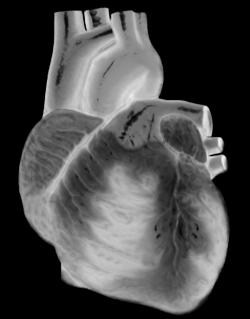

You take care of yourself - you eat right, don't smoke, drink in moderation and keep fit - but have you considered maths as a secret weapon in keeping you and your heart healthy? Dr Adelle Coster, a mathematician from the University of New South Wales, Australia, has just been awarded a three-year research grant to develop a mathematical description of how our hearts beat - a description that might one day save otherwise fit and healthy young people from dying unexpectedly of cardiac arrest.

We have natural pacemakers in our hearts that keep them pumping - the primary one is called the sinoatrial node. This generates a regular electrical impulse that is carried around a pathway of conductive tissue, causing our hearts to pump in a normal, regular rhythm. If our natural pacemakers stop working properly, abnormal heart rhythms called arrhythmias result. In serious cases, arrhythmias can lead to sudden cardiac arrest, which can be fatal if the victim doesn't receive treatment within minutes. And this is not just a danger for the old or unfit - experts believe that up to eight otherwise healthy young people (under the age of 35) die suddenly each week in the UK of cardiac arrest (for more information see Cardiac risk in the young and Sudden arryhthmic death syndrome).

"In this study, we are interested in how different areas of the heart communicate", says Coster. "We describe each area of the heart (for example the primary pacemaker, the sinoatrial node) by its state, or how active it is - causing a muscle contraction, recovering, etc. This is due to the underlying chemical state of each of the cells in that region."